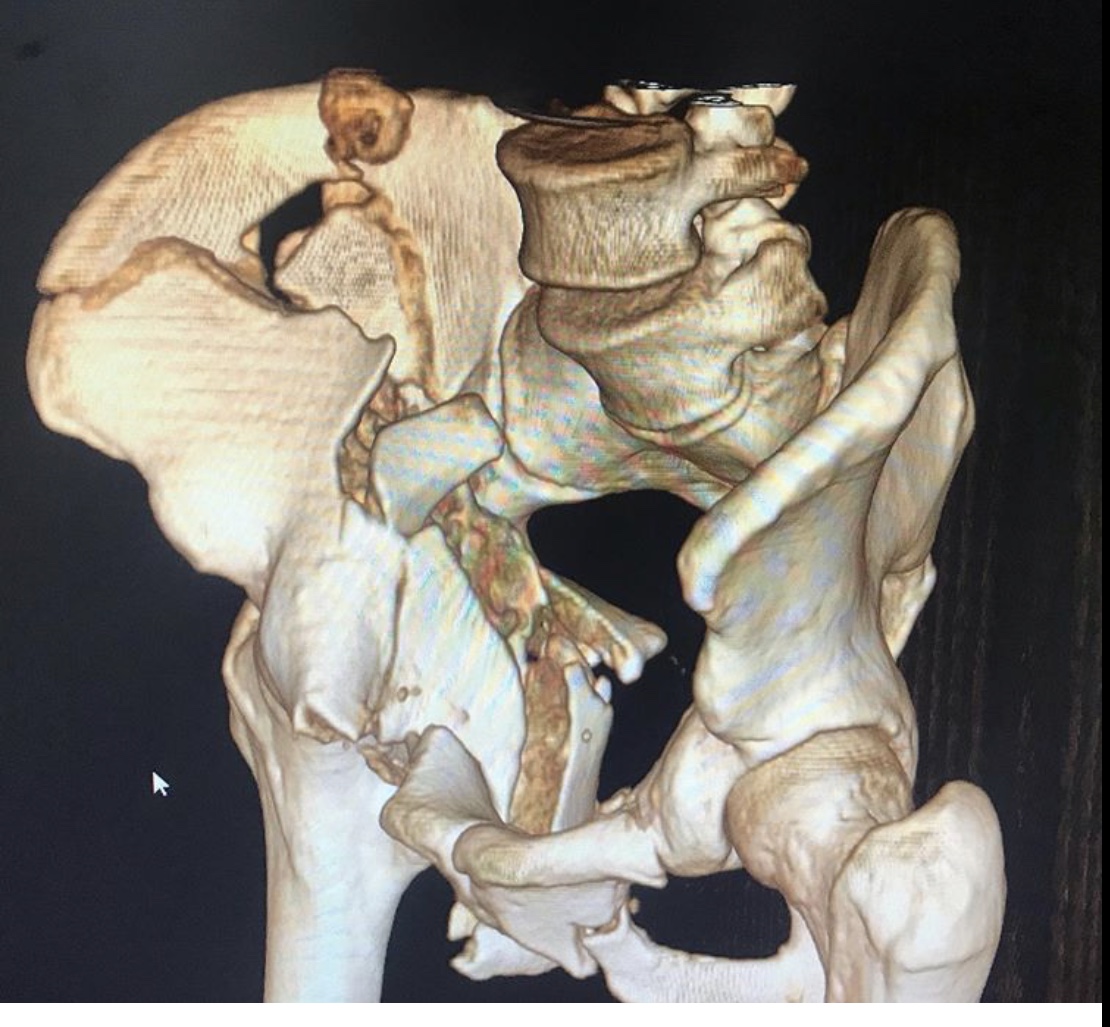

Но к врачам-травматологам Городской клинической больницы № 7 Казани этот пациент поступил лишь спустя месяц после травмы. Врач – травматолог клиники Руслан Закиров признается: «Они в другом городе лечились. Жизнь спасали. К сожалению, не во всех больницах есть возможности для хирургии таза».

Пациента, что называется, «собрали».

Была выполнена открытая репозиция, остеосинтез пластинами.